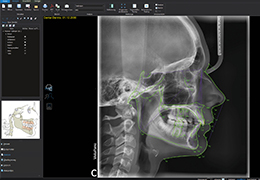

ANYTHINK 经导管主动脉瓣膜置换术分析系统